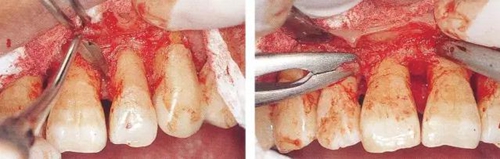

▼圖15-1  顯示牙齦翻瓣進(jìn)行齦下刮治和根面平整的圖像。不良肉芽組織的去除和包含SC/RP在內(nèi)的清創(chuàng)處理決定了牙周外科處理結(jié)果是否良好。

18.jpg

▼圖15-2(左)  不良肉芽組織去除后出血變少

▼圖15-3(右)  在進(jìn)行牙冠形成的牙齒上,可以用牙周外科用車針進(jìn)行SC/RP,手術(shù)時間得以大幅縮短。

19.jpg